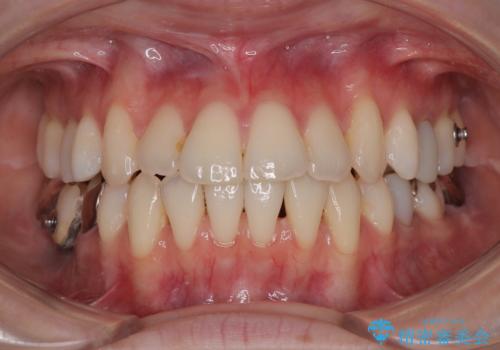

【モニター】前歯のデコボコをインビザラインで綺麗に

- 上下前歯のデコボコとクロスバイトを気にして来院された患者様です。

治療済みの処置歯が多いため、インビザラインを用いて矯正治療を行うこととしました。

下顎臼歯部にブリッジが装着されており、移動不可のため、IPR(歯と歯の間を削る)と歯列全体を拡大させることで、歯並びを整えていくこととしました。

インビザライン特有の奥歯の噛みにくさが治療後半に発現しましたが、無事に終了させることができました。